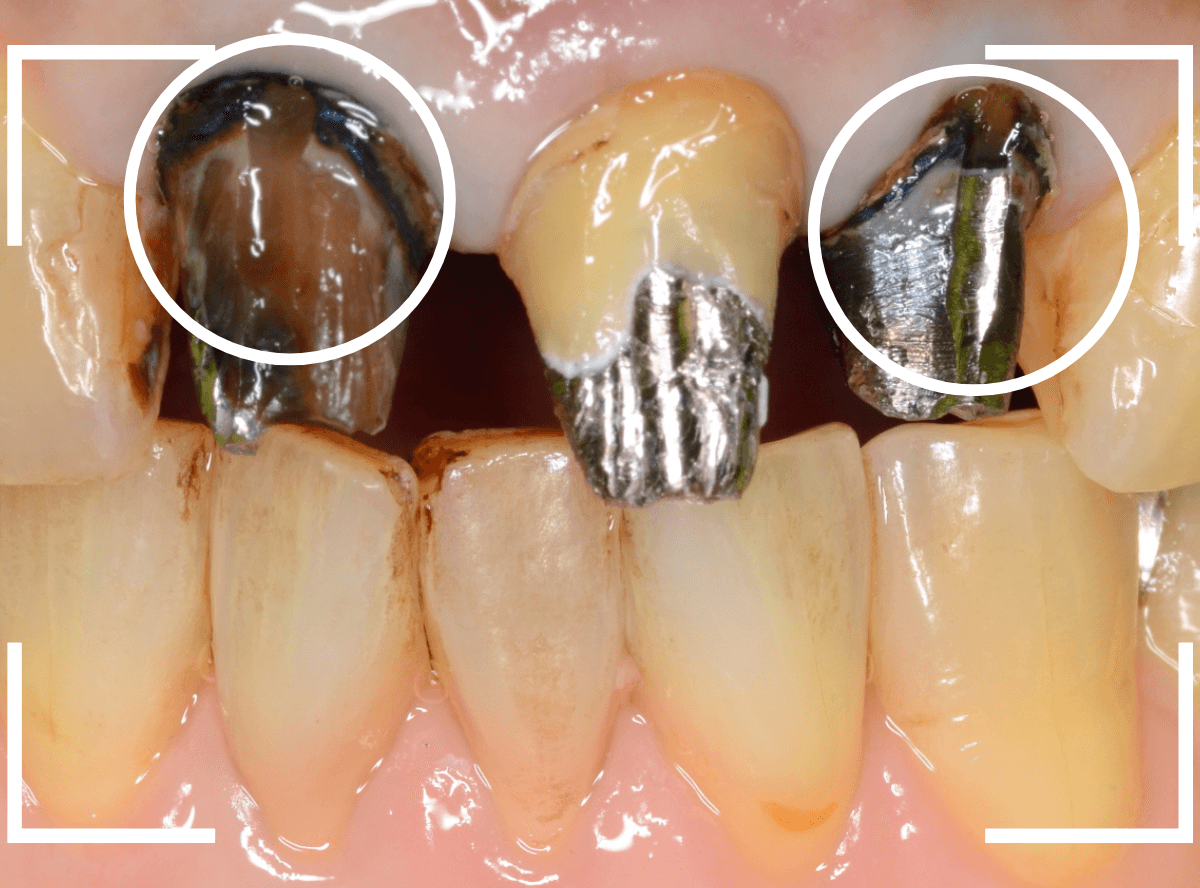

まず、前歯のさし歯を外します。

神経を取っている歯(無髄歯)ですので、痛みはありませんが、前後の2本は虫歯になっています。

これら、歯全体を覆うさし歯の中の虫歯はレントゲン写真でも写ってこないため、治療前に正確な判断ができません。

さし歯を外す時は、いつも想定外の虫歯などがないかどきどきします(><)

隣の歯の虫歯も顔を覗かせています。

虫歯を除去後に、裏側から撮影したところです。

思っていた以上に神経ギリギリ、歯全体に渡る大きな虫歯でした。

そのとなりの〇部の歯も同じように広くレジンをつめる治療をしてある中が大きな虫歯になっていました。

結局、5本ともさし歯で治療する必要がありましたので、審美性の高い、ジルコニア・セラミックで治療する事になりました。

手前の3本のメタル・コアも審美性の高いファイバー・コアに入れ替えて、全体の形態をトリミングします。